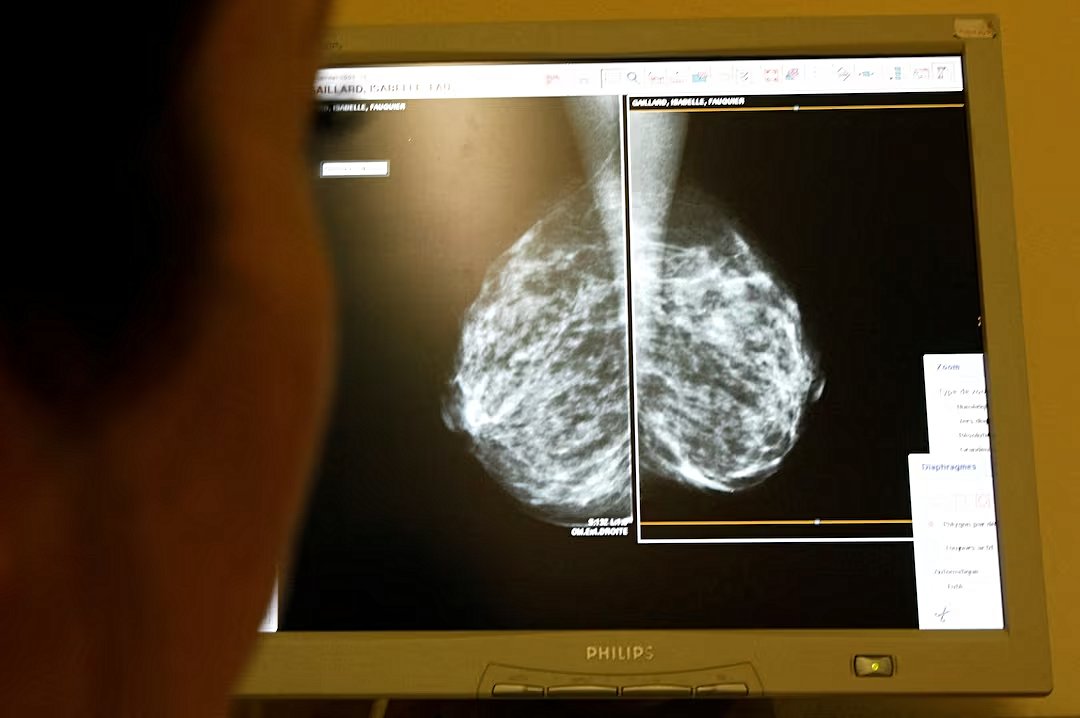

Pazartesi günü yayınlanan büyük bir çalışma, Afrika kökenli kadınlarda tespit edilen on iki meme kanseri geninin, hastalık riskini daha iyi tahmin etmeye ve Avrupa kökenli kadınlardan potansiyel risk farklılıklarını vurgulamaya yardımcı olabileceğini ortaya koydu. Araştırmacılar, bu bulguların meme kanseri risk skorlarını geliştirmek için önemli bir adım olduğunu belirtti ve siyah kadınların beyaz kadınlara kıyasla meme kanseri risk faktörlerini daha doğru bir şekilde değerlendirebileceklerini söyledi.